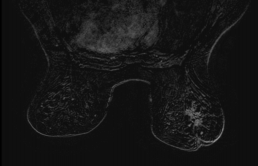

Patiente de 71 ans, masse palpable sein droit négativée 1 mois auparavant, consultation dans un second cabinet pour contre avis.

MammoScreen pointe la masse avec un score 9.

La masse est retrouvée en échographie et mesure 20mm. L’IRM donne une masse volumineuse.

Biopsie : CCI grade 3